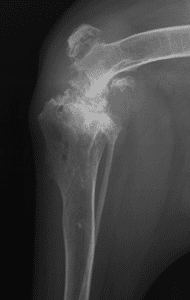

Total joint replacement of any joint carries the risks of possible complications. Therefore, total knee replacement is reserved for dogs with painful knee conditions, where either conventional surgical techniques have not been successful or where diseased joints are unresponsive to conservative management using pain relief and rehabilitation. The most common cause of knee pain is osteoarthritis secondary to cruciate disease, trauma or malformation of the knee. Examples of severe osteoarthritis are shown below: